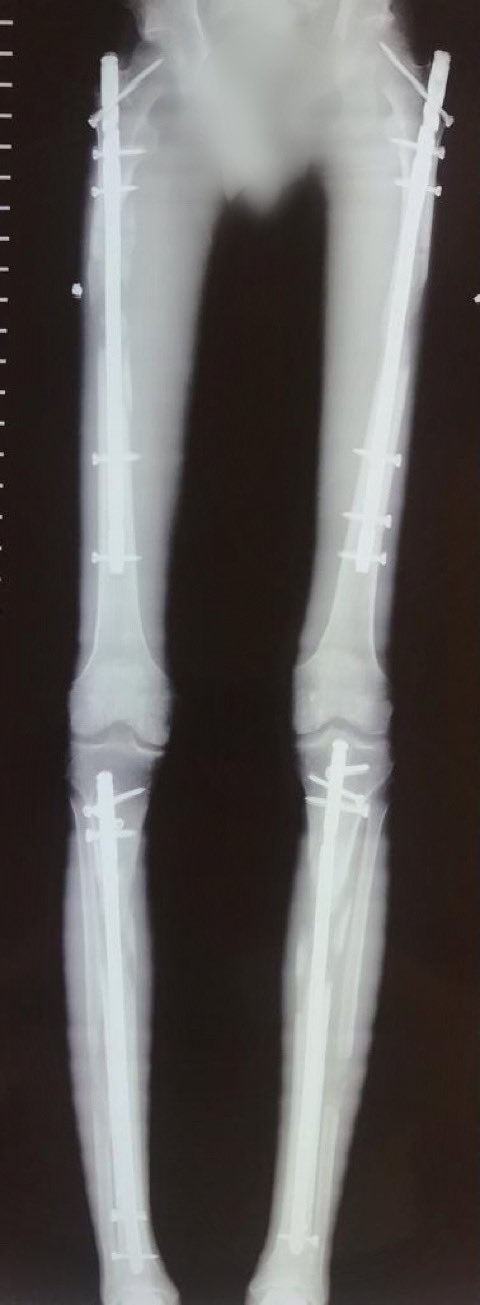

【ユピピ】骨延長手術を受けた157センチの男性、無事169センチの長身の身体を手に入れる

600万円で身長を12cm伸ばした25歳男性「手術費用は副業noteで貯めた」

今日最後のレントゲンを撮ったんだけど、ネイルはかなり腰から出てるんだな

そのせいか歩くと腰の側部が結構痛